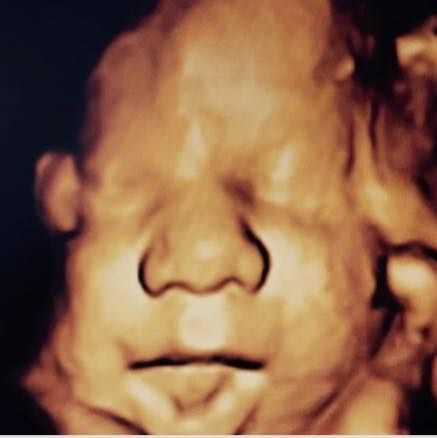

Fotoğraflar ve videolar

4 Boyutlu Renkli Doppler İkinci Düzey Ultrasonografi

4 Boyutlu Ultrason